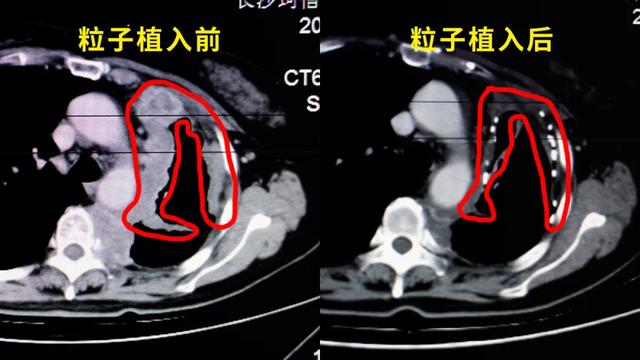

“饿死”肿瘤: 通过“栓塞术”,堵死为肿瘤输送养分的血管,断其粮草,让它自然萎缩。“毒死”肿瘤: 通过“动脉灌注”,将化疗药像“精确制导导弹”一样,只投送到肿瘤内部,实现高效杀灭,同时避免“毒害”全身。“烧死/冻死”肿瘤: 对引发疼痛、梗阻等症状的关键病灶,用微波/射频“加热”,或用氦氩刀“深冻”,进行定点清除,快速缓解痛苦。“内部瓦解”肿瘤(持久围剿): 这便是放射性粒子植入术。我们可以通过一根细针,将像米粒大小的放射性源直接植入肿瘤内部。让这些“深水炸弹”24小时、持续不断地从内部照射和摧毁肿瘤细胞,而对周围的正常组织损伤极小。这是一种“润物细无声”的持久战,尤其适合一些局部的、顽固的病灶。这一切的目的,不是为了追求一个虚无的“完全清除”,而是为了实现一个更现实、也更宝贵的目标:“带瘤高质量生存”——让你在有效控制病情的同时,还能吃得下、睡得着、有力气散步、有精神与家人说笑。 保住你作为人的基本生活质量和尊严。